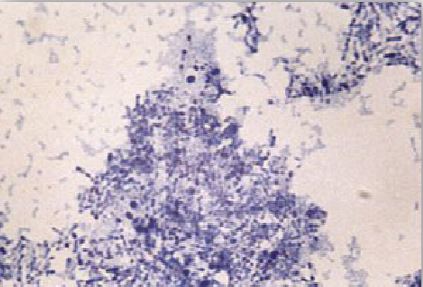

صيغة جرام لإفرازات الجروح تظهر وجود مستعمرات النوع البكتيري C. diphtheriae

أما في حالات الإصابة الجلدية فإن هذا النوع البكتيري يمكن ان يحدث الإصابة من خلال الجروح، من النادر في هذا النوع من الإصابات أن تحدث مضاعفات خطرة. تنتشر هذه الإصابة الجلدية في العديد من الدول النامية وخاصة في المناطق الريفية مما يكسب الأشخاص المصابين مناعة مبكرة للوقاية من النوع البكتيري C. diphtheria الأمر الذي قلل من معدل حدوث الإصابات التنفسية .